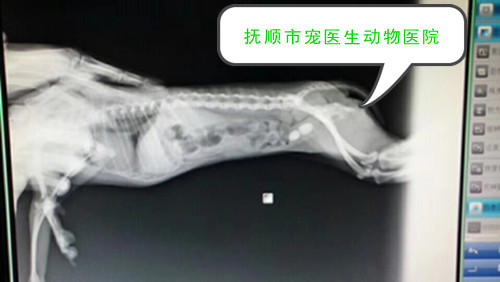

抚顺动物医院 抚顺宠物医院哪家好 抚顺宠医生动物医院 抚顺宠物医院